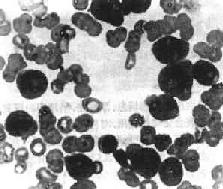

1.周围血像早期即出现贫血,白细胞总数多少不等,白细胞增多性与不增多性者约各占一半。白细胞增多性者,白细胞总数多在2万~5万/μl,常呈进行性上升,可高达10至数10万。其中有大量原始和幼稚细胞(图11-6)。白细胞不增多性白血病的白细胞计数可正常或减少,有时可降低至1000~3000/μ1,较难找到原始或幼稚细胞。血小板减少有时达1万/μ1以下。

图11-6 急性粒细胞性白血病

周围血内有大量原始粒细胞